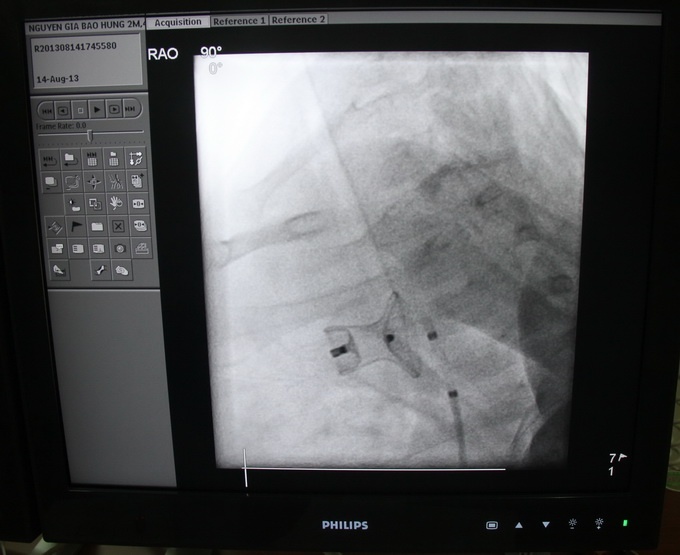

| Bác sĩ đã can thiệp đặt dù có đường kính 10/8 mm để lưu thông máu. |

Sau hội chẩn, các bác sĩ đã tiến hành can thiệp đặt dù có đường kính 10/8 mm, bít ống mạch máu lại. Sau can thiệp, sức khỏe bệnh nhân đã ổn định, áp phổi tốt. Do bệnh nhi bị bệnh gần 3 tháng nên bị biến chứng dẫn đến suy tim, viêm phổi nên đang tiếp tục được điều trị.